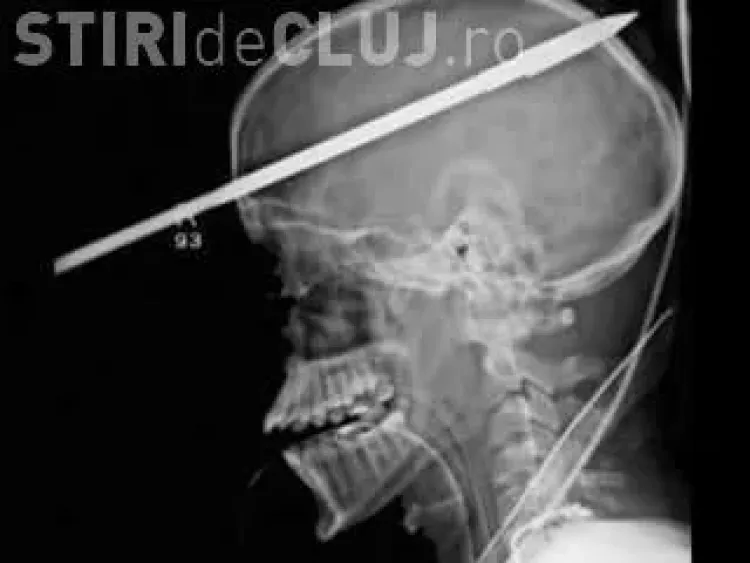

Un bărbat a supraviețuit în mod miraculos, după ce s-a împușcat în cap cu un harpon, iar suliță i-a străpuns creierul.

Yasser Lopez, 16 ani, din Florida, încărca un harpon împreună cu prieten, dar s-a împușcat în cap.

"Lancea a pătruns prin cap, începând cu doi centimetri deasupra ochiului drept și aproape a ieșit pe partea cealaltă. Dacă puneai mâna pe piele puteai simți vârful ei", a declarat Dr. George Garcia, chirurgul care l-a examinat.